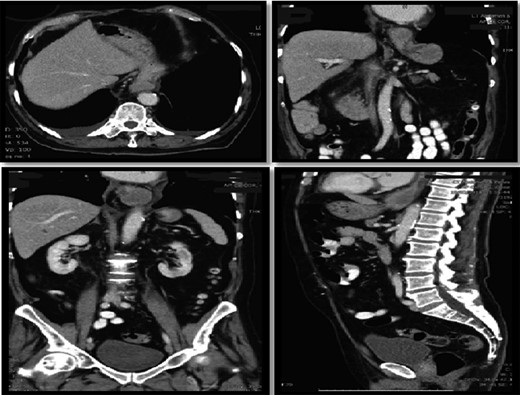

Computer tomography pulmonary angiogram (CTPA) done given recent surgery reported distal esophagus perforation with bibasal pleural effusion. No pulmonary embolism (Fig. 1).

Hiatus hernia with associated mural thickening of esophagus and locules of gas showing localized perforation.